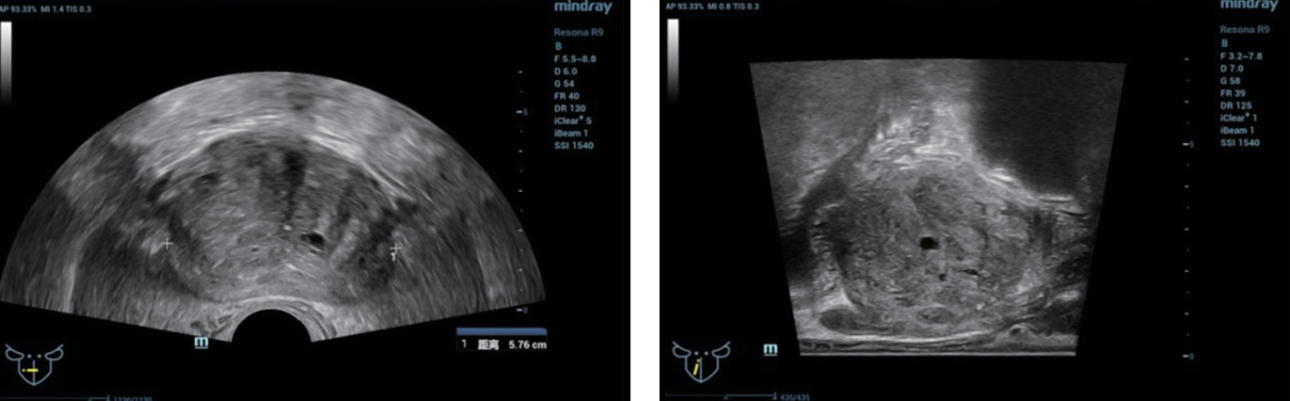

TRUS finding (figure 1):?

- Prostatic hyperplasia with calcifications and small prostatic cysts.

- Heterogeneous prostatic echotexture with no discrete lesion identified.

Preoperative discussion: As the suspicious lesion could not be identified on conventional ultrasound, the patient was scheduled for a targeted perineal prostate 12-point systemic needle biopsy under TRUS/MRI fusion guidance.

TRUS-guided biopsy combined with PSA is an important method for the diagnosis of prostate cancer (PCa). Peripheral zone hypoechoic nodules are a typical sign of PCa, however, in early PCa these lesions appear isoechoic in many cases which makes differentiation from prostatic hyperplasia and low-grade prostatic intraepithelial neoplasia difficult and can result in missed diagnosis [1]. In this case, PSA was increased, but no suspicious lesions were detected on TRUS imaging.